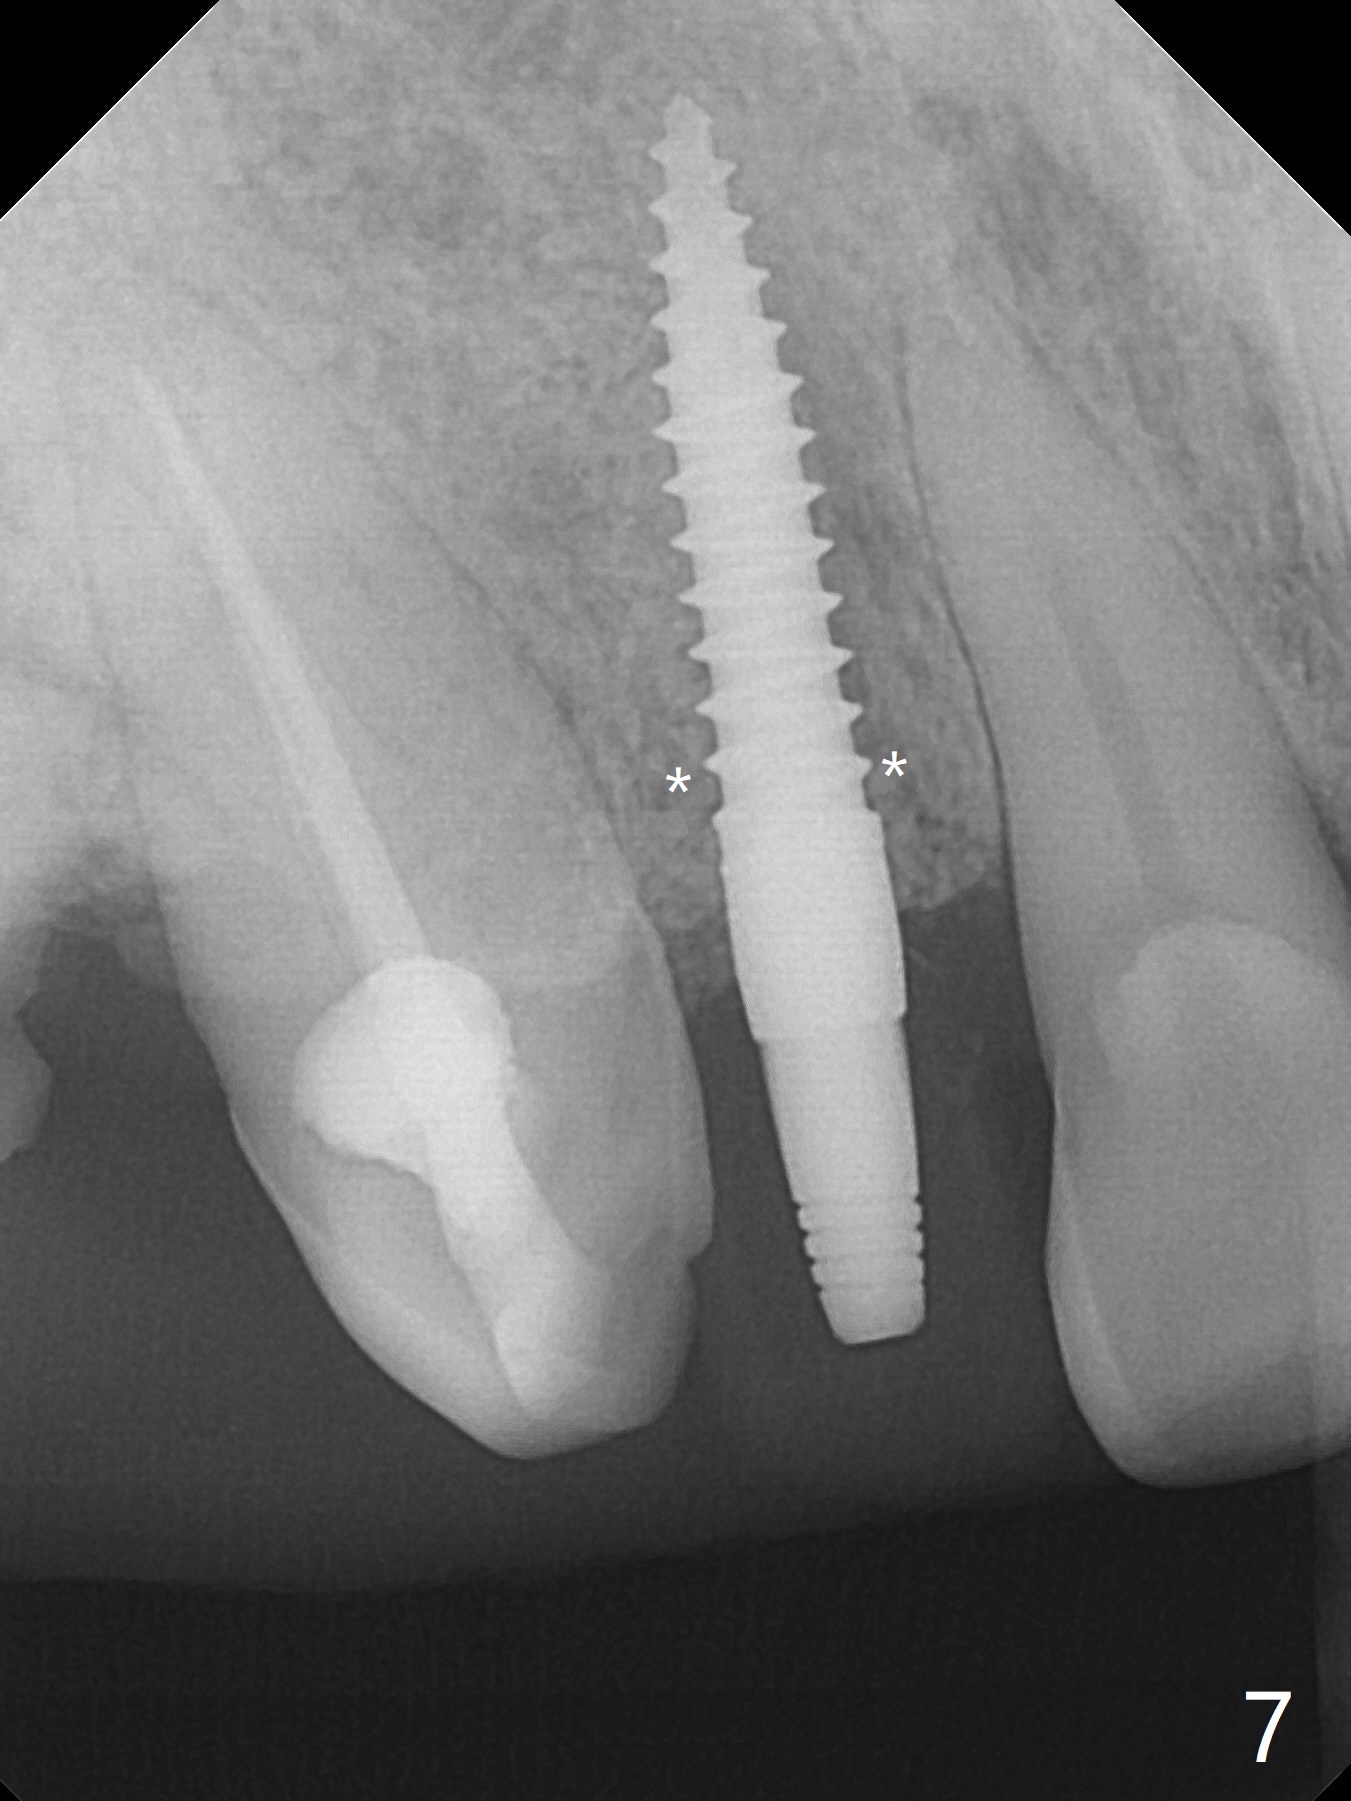

An apical abscess is present when the patient returns for immediate implant at #7 (Fig.1 *); a 2nd challenge is deep bite. After smooth extraction, the apical buccal plate is found to be perforated. Following debridement, a piece of gauze is placed in the apical defect for hemostasis, while osteotomy is initiated palatal (Fig.2). The apical defect seems to be extensive (Fig.3 yellow dashed line). A new trajectory is intended (red arrow) without much success. Before implant placement, bone graft is placed in the apical defect defect area, while a drill (Fig.4 D) is inserted in the finished osteotomy (Fig.5 O). In spite of seemingly large apical defect, the buccal crest bone exists (Fig.4 x). A 3x14(2) mm 1-piece implant is placed with stability; the first round of bone graft is apparently around the apical portion of the implant (Fig.6 *). The coronal end of the implant has to be adjusted several times buccopalatally to accommodate the deep bite. A 2nd round of bone graft following an immediate provisional closes the coronal space of the socket (Fig.7 *). CT will be taken to show the bone graft to repair the buccal plate defect when the patient returns for postop follow-up. In fact the defect is minimal in CT a month ago. The fistula does not disappear 1 week postop, but it is non tender (Fig.8). The patient complains of asymptomatic swelling in the right nostril. CT shows that the large buccal perforation is repaired with large amount of bone graft (Fig.9,10 *). It would be nicer to place the implant slightly more buccal apically (Fig.11 red lines; Fig.12 (preop design)). The buccoapical fistula disappears nearly 1 month postop (Fig.13). The apparently "lifeless" bone graft seems to be harmonious with the surrounding tissue (Fig.14). The periimplant gap reopens with implant mobility nearly 4 months postop (Fig.15), which is related to micro-movement associated with the immediate provisional. The latter is removed. A larger 2-piece implant will be placed in a 2-staged manner if needed (Fig.16). In fact the 3x14 mm straight 1-piece implant (Fig.17) has no mobility when it is retightened, but the trajectory remains buccal. Incision shows that there is no implant thread exposure. A 3x14 mm 15 degree angled 1-piece dummy implant is able to establish the correct trajectory, but there is no occlusal clearance (Fig.18). Micromovement during osteointegration may recreate loosening. Finally using Lindamann bur, the osteotomy is changed so that a 3.5x13 mm 2-piece implant does not need an angled abutment to establish occlusion (Fig.19). There is one palatal thread exposure. Allograft is placed circumferentially, followed by Human Amnion-Chorion Allograft and Collagen Plug. The wound does not heal 8 days postop (Fig.20), as related to the age (79 years old)? The wound appears to heal with a membrane on the surface (Amnion-Chorion one?) 3 weeks postop (Fig.21). The ridge looks wide 3.5 months postop (Fig.22,23). A 4.5x5.5(3) mm appears to be seated incompletely with a gap between the abutment and the implant (Fig.24<). A provisional is fabricated after heavy palatal reduction. Two months later, the provisional fractures. After repositioning the abutment with complete seating and torque (Fig.25), impression is taken. Although the buccal plate is concave, the gingiva remains healthy 10 months post cementation (Fig.26,27).